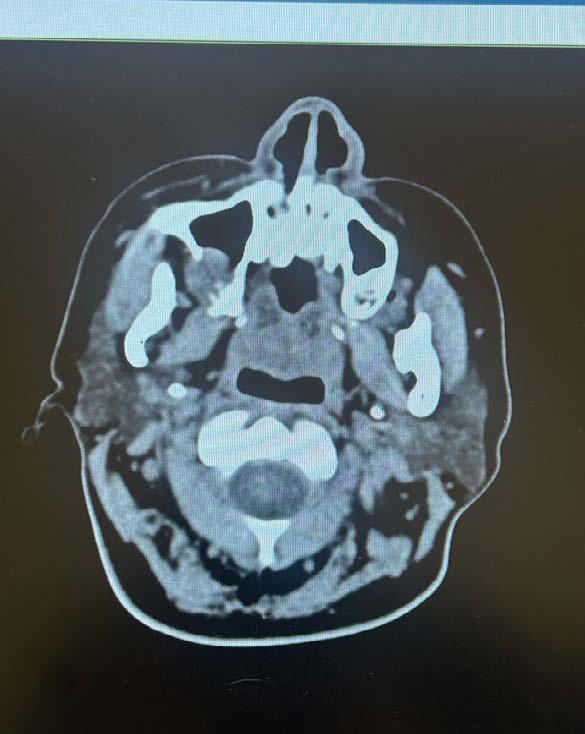

En 2025, la paciente presentó cefalea que posteriormente se localizó en la región maxilar. En consulta externa se realizó la exodoncia del órgano dentario 17 (Figura 2). Debido a la persistencia del dolor y la aparición de una lesión en la tuberosidad maxilar, se llevó a cabo una biopsia, cuyo resultado histopatológico fue compatible con metástasis de carcinoma ductal. Se documentó una lesión sólida de 21 mm que comprometía el hueso maxilar superior derecho, con destrucción ósea e impronta en el seno maxilar. Además, se observó compromiso del espacio graso retromaxilar, así como adoncia del segundo y tercer molar superiores derechos y ganglio submandibular derecho de 11 mm, con características sugestivas de infiltración tumoral (Figura 3).

La evaluación imagenológica mediante tomografía de maxilar y radiografía panorámica mostró una lesión lítica en el lado derecho (Figura 4). Presenta datos de recurrencia de la enfermedad a nivel sistémico en hígado, hueso y pulmón. Ante estos hallazgos, el servicio de mama decidió iniciar tratamiento radioterapéutico dirigido a la región pterigopalatina derecha, administrando una dosis total de 20 g y en 5 fracciones.